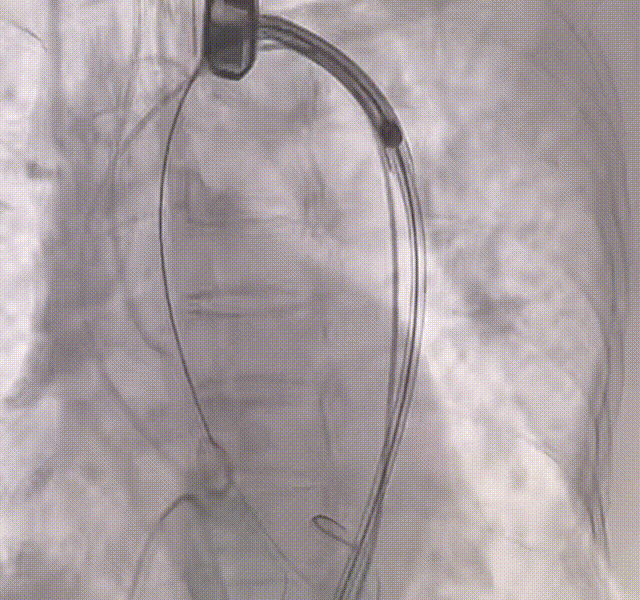

许金鹏教授 安徽省胸科医院 干瓣耐久首选之,15年承诺佑病患:随着病患的复杂性提高及TAVR二次手术窗口期的慢慢到来,摆在临床面前的是如何提升瓣膜使用的耐久性?预装干瓣的获批上市无疑为临床提供了全新的选择。预装干瓣摆脱了传统戊二醛保存的束缚,通过专利抗钙化技术及干式保存工艺打造了一款兼具“曲柔性”和“不沾钙”瓣叶的介入瓣,预期会有更耐久的使用寿命。此次病例患者小瓣环,Prostyle A®自膨瓣的收腰设计,为冠脉开口预留了“生命通道”,而平衡的收腰设计又很好的保证了开口面积,为小瓣环患者血流动力学提供的牢靠的保障。 期待这样一款基于临床需求的性能平衡的耐久干瓣,护佑 TAVR广大患者的全生命周期管理! 患者病史 主要诊断:非风湿性主动脉瓣狭窄(重度);非风湿性主动脉瓣关闭不全(中度);非风湿性二尖瓣关闭不全(中度);心脏扩大(左房明显扩大、左室略大);肺动脉高压(估测肺动脉收缩压约 39mmHg);胸椎压缩性骨折(T9 椎体,考虑新鲜);肺部阴影(两肺慢支改变、多发结节);胆囊术后; 入院检查:BP 109/60mmHg、心率 77 次 / 分(律齐),神清精神可,口唇不绀。 术前超声提示 主动脉瓣钙化并狭窄(重度)伴反流(中量),Vmax509cm/s,PGmax105mmHg;升主动脉增宽;左房明显增大,左室略大;二尖瓣关闭不全伴反流(中+量);瓣尖轻微增厚;室间隔增厚; 术前CT 三叶瓣(L-N融合,功能型二叶瓣),瓣叶增厚中度钙化,钙化主要分布在左冠窦瓣叶边缘及左无融合处、右冠瓣叶基底及边缘,主动脉瓣环径22.2mm,LVOT21.1mm,呈略直通型;双侧冠脉开口高度可,窦部空间大,VTC距离够,预估冠脉低风险,STJ、升主动脉内径可;左室内径可,主动脉水平夹角47°,非横位心。主动脉弓角弓距可;外周入路无明显迂曲,无钙化,两侧股动脉内径可,均可通过20F大鞘,右股低分叉。 手术策略 推荐右侧股动脉为主入路,左侧股动脉为辅助入路,使用20F大鞘,右股分叉上方1cm穿刺。推荐选择AV23瓣膜,18mm球囊预扩,最终理想位置瓣下2mm。 手术过程 在右股动脉穿刺建立通路后,顺利送入大鞘,经食道超声及血管造影确认路径稳定。18mm球囊预扩后评估冠脉灌注良好,后将Prostyle A® AV23瓣膜精准释放于目标位置,超声显示无瓣周漏,术后即刻造影显示无明显反流,导管测平均跨瓣压差8mmHg,心功能明显改善,患者生命体征平稳。 主动脉根部造影 18号球囊预扩 输送器顺利过弓 迅速锚定,平稳释放至工作位 最终造影,位置形态良好,无瓣周漏 Prostyle A®预装干瓣——助力临床最优化解决方案 预装干瓣 便捷顺安:金仕生物专利抗钙化技术运用纳米技术去除组织内的细胞碎片和磷脂,封闭游离醛基,从根本上阻断了瓣膜钙化的多项因素,显著提升了瓣膜的耐久性;同时,相比较传统戊二醛保存方式,干式存储最大限度的保留心包的亲水亲油平衡,还原组织天然曲柔性,进一步保障了瓣叶开合,保证长期耐久性; 流入端桶状设计:流入端桶状的设计,迅速稳定锚定,减少手术时间的同时进一步保障了术中安全; 平衡的收腰设计:该病例左冠高度10.8mm,AV23瓣膜的平衡收腰设计既确保了冠脉开口安全性,又保证了EOA,有效降低了循环崩溃风险,而术后8mmHg的压差的表现更加证明了优秀的血流动力学,进一步提高了瓣膜的耐久性。 专家简介 许金鹏 安徽省胸科医院(点击查看专家详细简历) · END ·